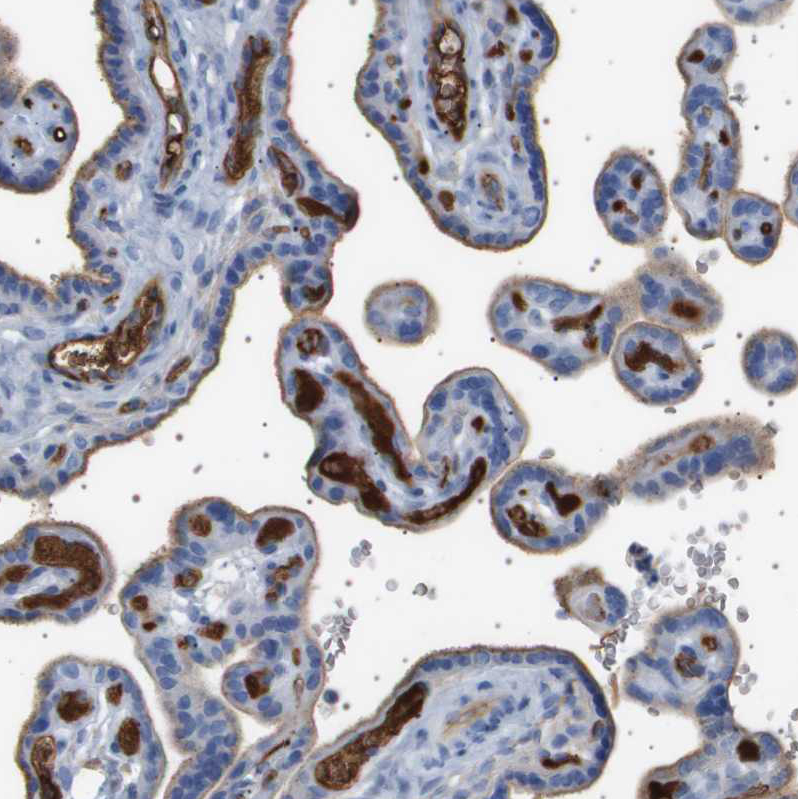

Immunohistochemical staining of human tonsil shows strong cytoplasmic positivity in germinal center cells.